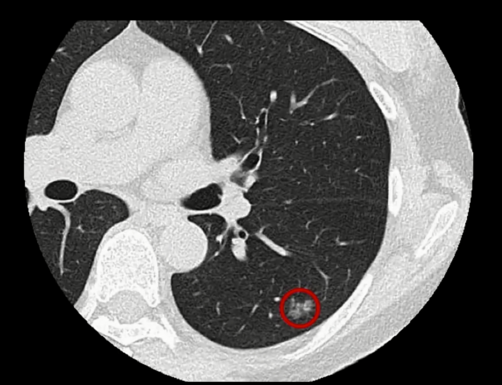

这是泷川的肺部CT扫描图,图上左肺红色圈起来的部分就是癌症所在的位置,有1.3厘米大,最后确诊为腺癌I期。

腺癌占肺癌病例的80%以上,通常肿瘤在肺的末梢部分生长,那里没有感觉神经,所以早期很难发现。

泷川很幸运,她的癌症还在初期,因为这种肺癌早期没有什么症状。初期腺癌可以做手术切除,医生选择用一种日本研发的新技术为她进行手术。